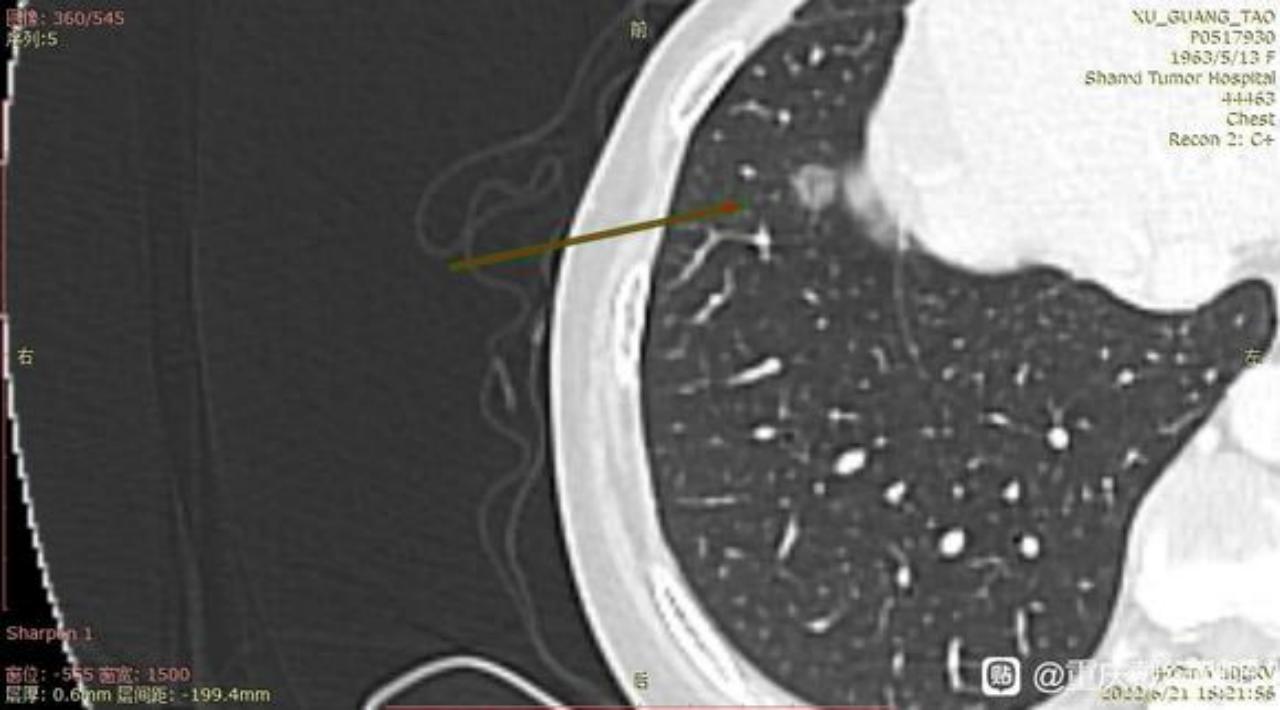

主任前段时间已经麻烦过您了,术后病例确实跟您的判断一样,左肺上叶结节为早期肺腺癌(腺泡型)。当时我们医生先是进行了楔形切除,中间又出来谈话进行了叶切。(患者我母亲,59岁女性,不抽烟喝酒)现在术后病例出来了:腺泡型肺腺癌、大小2cm*1.5cm*1cm,支气管、淋巴结未见累计。

3、主任,根据您之前判断,右肺下页的0.7毫米磨玻璃结节至少是微浸润。现在医生给切了左肺上叶,后面手术多久能进行啊?是不是难度很大了?